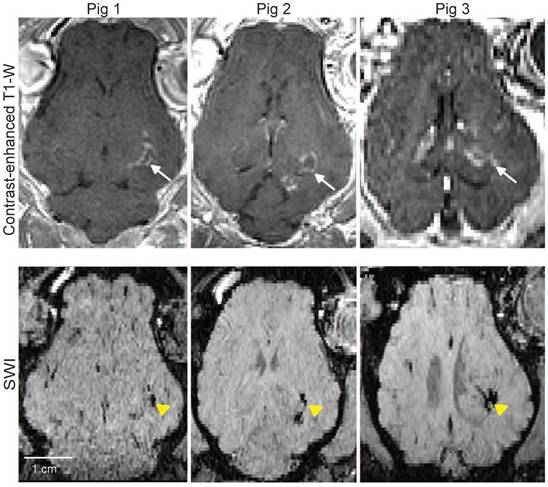

Figure 6 shows representative contrast-enhanced T1-W (top row) and SWI (bottom row) images following FUS treatment. The FUS treatment resulted in distinct microhemorrhages, visible as hypointense regions on SWI (yellow arrowheads), indicative of vascular injury. Consequently, this highlights the critical need to optimize FUS parameters to ensure safety without compromising therapeutic efficacy.

Figure 6

MRI safety evaluation. Representative horizontal MRI images of pig brains. Top row: Contrast-enhanced T1-W images show localized signal enhancement at the targeted brain regions (white arrows), confirming successful FUS targeting. Bottom row: Corresponding SWI reveal microhemorrhage in the targeted regions (yellow arrowheads).